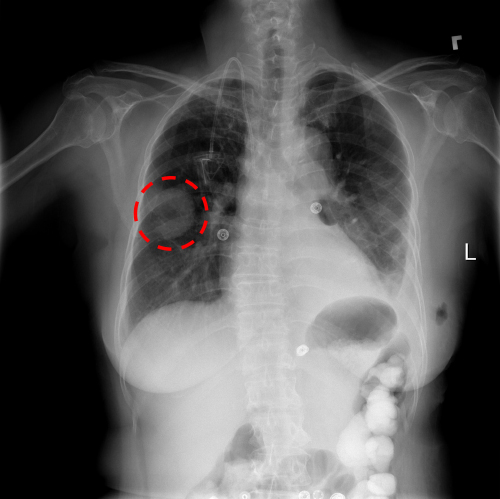

A chest x-ray identifies a lung mass.

Chest x-ray identifies a lung mass.